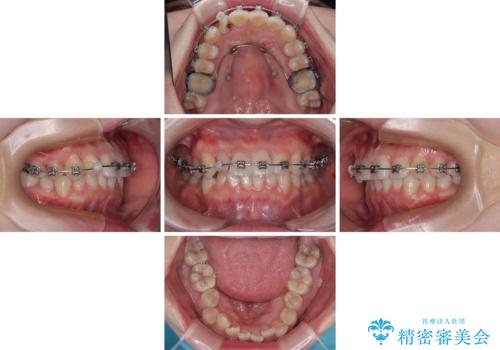

- メタルブラケット

マウスピースでもワイヤーでも対応可能でしたら、捻転が非常に強いことから、患者様と相談の上ワイヤー装置にて矯正治療を行うこととしました。

捻転を解消する際に、歯列全体が前方に突出して出っ歯の仕上がりとなることが懸念されたため、補助装置を用いて上顎歯列全体を後方に移動する力をかけることとしました。